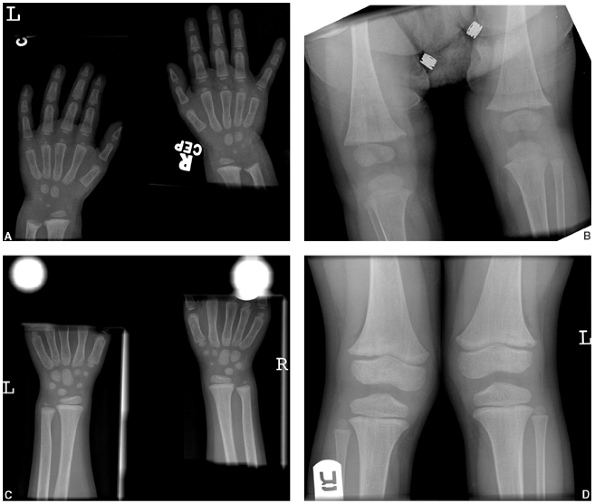

![]() |

Figure 7.4 Rickets. Changes caused by rickets can be seen (A) at the wrist and (B)

at the knees of this 1-year-old child with X-linked hypophosphatemia. The growth plates are widened and the metaphyses are cupped, particularly at the ulna and femur. At 4 years of age (C, D) the changes have resolved with medical treatment. |